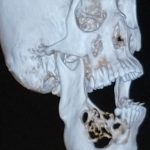

Las radiografías o Rayos X son una herramienta empleada en el campo de la Medicina para obtener imágenes del interior de los cuerpos al exponerlos a una fuente de radiación controlada.

A través de este método, se facilitan los diagnósticos médicos sin necesidad de cirugías exploratorias o invasivas.

Los rayos X son como una luz que atraviesa la piel, pero no puede atravesar los huesos.

Por eso se ven tan bien en la imagen radiográfica.

Las imágenes de rayos X muestran el interior de su cuerpo en diferentes tonos de blanco y negro. Esto es debido a que diferentes tejidos absorben diferentes cantidades de radiación. El calcio en los huesos absorbe la mayoría de los rayos X, por lo que los huesos se ven blancos.